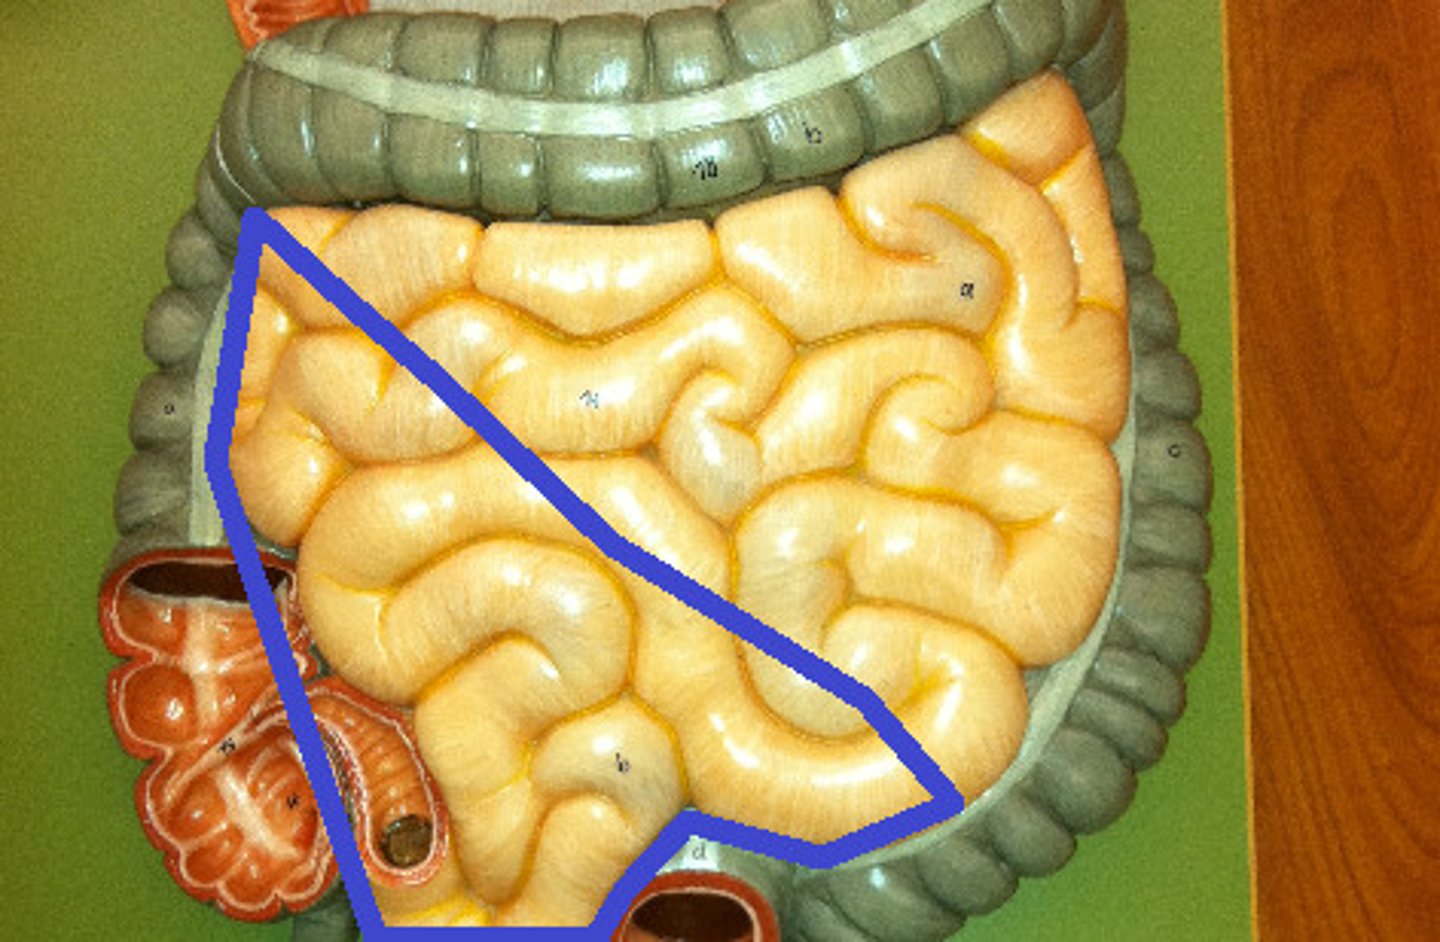

GI anatomy pin test

128 Terms

jejunum

ileum

ileocecal junction

cecum

appendix

ascending colon

transverse colon

descending colon

right colic flexure

left colic flexure

sigmoid colon